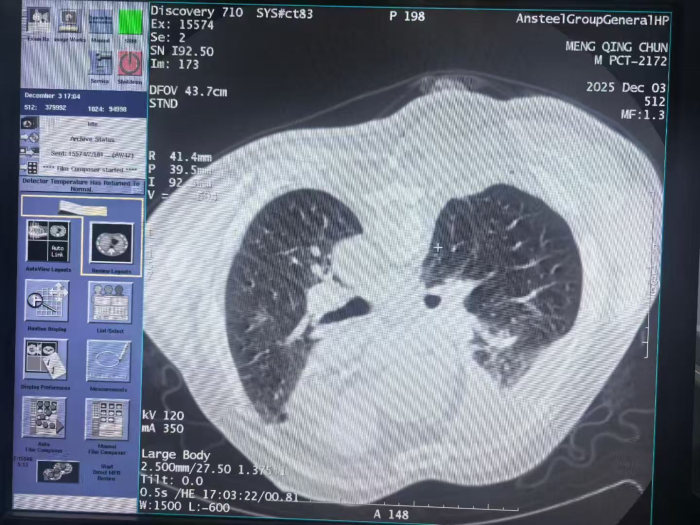

△术中

△术后无出血、无气胸

术后,患者孟先生恢复迅速,无任何不适,复查影像确认无出血、无气胸。此次手术的成功,具有多方面意义: